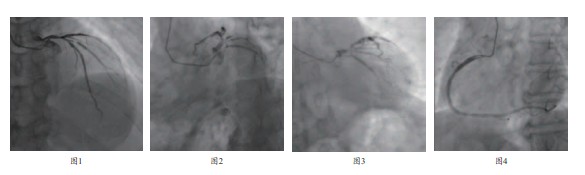

• 心脏彩超:三尖瓣中度返流,二尖瓣轻度返流,右房增大,左室舒张功能减退,LVEF :66%,5F TIG 造影管经桡动脉造影(图1~4)。

• 左冠:LM 末端狭窄约60%,LAD 近中段狭窄75%,第一对角支开口及近段狭窄80%,LCX 近段狭窄85%,两条中间支

• 右冠:近段局限性狭窄70%,其它分支血管无明显狭窄,远端血流TIMI 3 级。